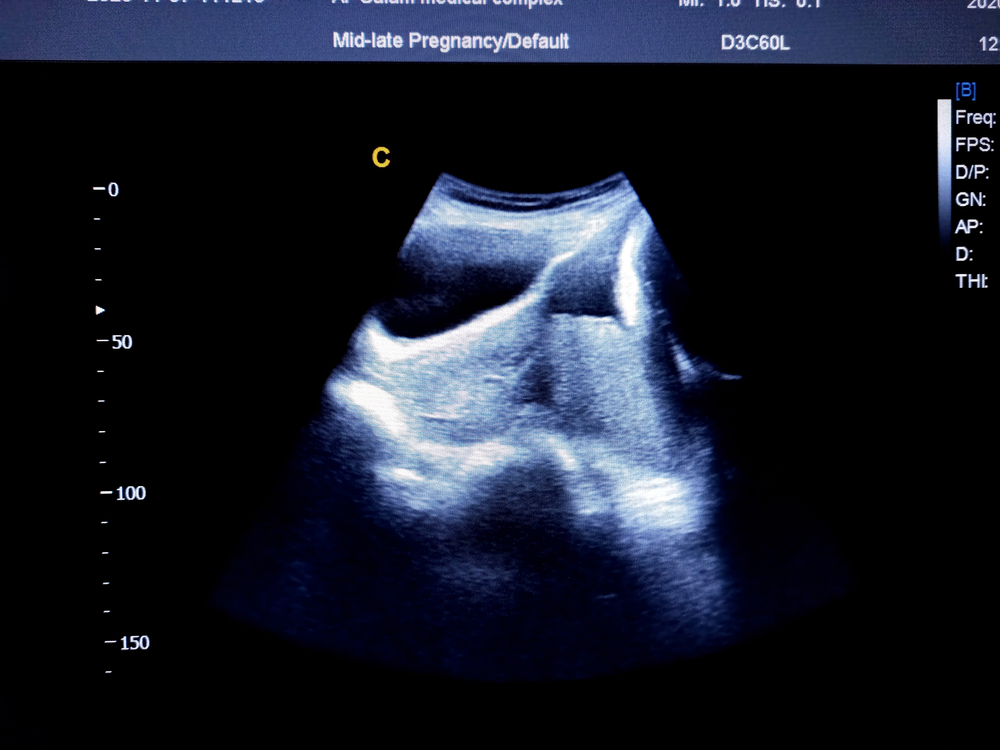

Sa panahon ng pagbubuntis, ang mga ina ay bumuo ng isang organ na tinatawag na inunan (placenta) sa kanilang matris. Nagbibigay ito ng oxygen at nutrients sa mga sanggol habang lumalaki ito sa loob ng sinapupunan ng kanilang ina. Karaniwan, ito ay nakakabit lamang sa mga dingding ng matris. Gayunpaman, ang placenta previa ay nangyayari kapag ang inunan sa loob ng sinapupunan ay bahagyang o ganap na sumasakop sa cervix. Kung ikaw ay kasalukuyang isang buntis na ina, maaari kang mag-isip kung paano maiwasan ang placenta previa.

Ang placenta previa ay isang problema na nangyayari kapag bahagyang o ganap na natatakpan ng inunan ang cervix ng ina. Ito ang gateway sa pagitan ng matris at puki.

Ang sanhi ng komplikasyon na ito ay hindi pa rin alam. Ngunit may ilang mga kadahilanan na maaaring mag-ambag sa iyong mga pagkakataon tulad ng bilang ng nakaraang pagbubuntis at ang edad. Ang kondisyong ito ay kadalasang makikita sa panahon ng pagbubuntis na may madalas na pag-check-up mula sa iyong doktor.